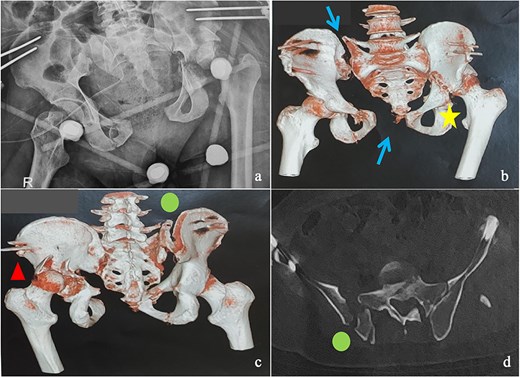

This was a 42-year-old male patient with no previous medical history who was admitted to the intensive care unit for treatment of polytrauma: severe chest trauma and pelvic trauma. During his stay in intensive care, the patient developed a pulmonary infection complicated by septicemia, requiring prolonged antibiotic therapy and thereby contraindicating any internal surgical fixation. After hemodynamic and respiratory stabilization, he was transferred to our department 40 days after the trauma with the following injuries: an unstable pelvic ring fracture classified as Tile-AO B1-2 [4]: disjunction of the pubic symphysis, disjunction of the right sacroiliac joint, and an ipsilateral crescent fracture classified as Kumar-Day 2 [5], along with a transverse–posterior wall fracture of the left acetabulum associated with a posterior dislocation of the hip, which was initially reduced but remained unstable. Fixation was performed using a Hoffmann II external fixator applied to the iliac crests with poor reduction (Fig. 1). He presented with complete weakness of the left foot dorsiflexors, with preserved sensation and no urogenital or abdominal complications. ORIF was performed in two stages, 5 days apart. The first stage consisted of performing the first two windows of the ilioinguinal approach: the lateral window to access the sacroiliac joint and the middle window to access the lower part of the sacroiliac joint and remove the osteofibrous callus. A Pfannenstiel approach was used to remove the callus at the pubic symphysis and fix it with a plate. The patient was then placed in the prone position and a posterior approach to the right sacroiliac joint was performed to carry out the same procedures on the posterior part of this joint and to perform fixation using ilioiliac and iliosacral screws. The second stage of the operation involved acetabular surgery. Given the chronic dislocation of the left hip, an anterior approach to the hip was performed to remove the intra-articular fibrosis facilitating the subsequent reduction of the femoral head. A Kocher-Langenbeck approach was then performed to remove the callus, reduce the femoral head and fracture, and fix it with a plate (Fig. 2). Postoperatively, the patient retained neurological deficits. At 6 months, the patient was able to walk without assistance and had a Harris Hip Score (HHS) score of 80 and Majeed score of 75 [6, 7].

Immediate postoperative X-rays. (a) Anteroposterior pelvic X-ray. (b) Inlet view of the pelvis. (c) Alar oblique view of the pelvis. (d) Obturator oblique view of the pelvis.